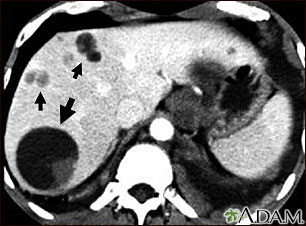

Esta TC muestra múltiples quistes en el hígado causados por la tenia de perro (Echinococcus). Se puede ver un quiste grande circular (en el lado izquierdo de la pantalla) y múltiples quistes más pequeños esparcidos por todo el hígado.